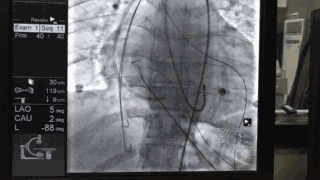

经右侧股静脉穿刺送入Swats鞘及房间隔穿刺针穿刺房间隔到达左房,送超滑丝经过左房,二尖瓣,左室-主动脉瓣至升主动脉,降主动脉 静脉肝素3000u,每1小时追加1000u。

穿刺股动脉并送入造影导管并内置圈套器,降主动脉中圈套长钢丝并抓出体外,在牵拉钢丝过程中使股动脉中的造影导管与房间隔穿刺鞘重叠组套,建立动静脉轨道。

将撤出的导丝调转方向(软头朝前)经该自股动脉造影导管重新送至右心房,下腔静脉。经锁骨下静脉可撕开长鞘送入圈套器,于下腔静脉中抓捕导丝后从锁骨下静脉拉出体外。